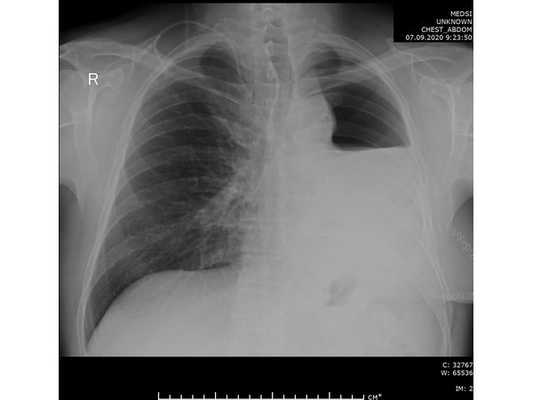

Проведена профилактическая стандартная антибактериальная терапия в течение пяти суток. По данным контрольной рентгенографии, отмечено смещение средостения в оперированную сторону.